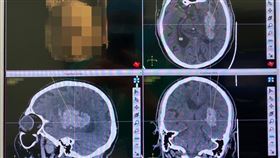

金鐘影帝留遺言!17小時手術「拆彈」搶命

07:18